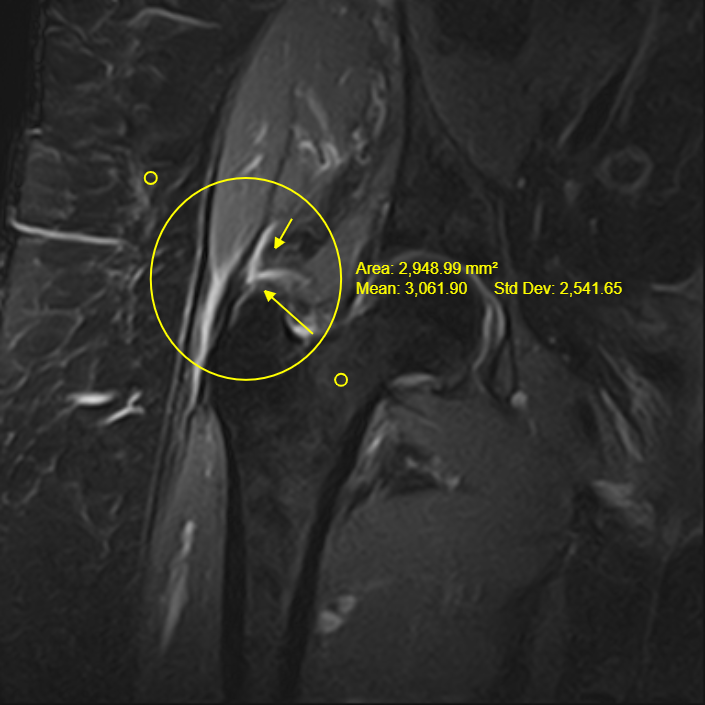

Davant la sospita de lesió dels tendons de la musculatura glutea es decideix demanar un RM del maluc que confirma l'arrencament d'aquests tendons a nivell de la seva inserció al trocanter.